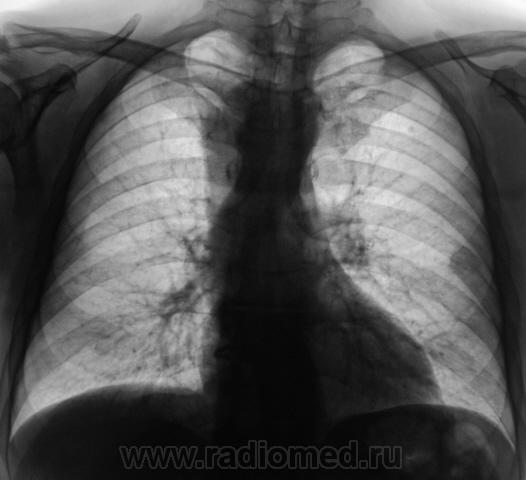

При расшифровке флюорограмм пациент взят на контроль. Жалоб не предъявляет.

Очень интересно! Третий раз подхожу к компу втечение дня... Овоидная тень с четкими ровными контурами, расположена субплеврально (или в средостении? Как будто трахею оттесняет), неоднородной структуры. В легочной ткани участок инфильтрации с мощной "дорожкой" к корню. Пожалуй, выскажусь за инфильтративный ТБС и туберкулому. А переломчик VII ребра слева похож на относительно свежий.

Считаю важным осмотр щитовидной железы на УЗИ и вилочковой, если возможно, вероятны их изменения, которые проявились на данной рентгенограмме. А в S2 слева единичный кальцинат. И консолидированный перелом 7 ребра слева по задней подмышечной линии.

Пожалуй процесс исходит из средостения и явно "злой"....

А где это все на боковой? Зато аорте какая красавица! Может это она и есть?

А может это праволежащая аорта?

Да, вроде как dextra-позиция аорты, под скопией бы глянуть.